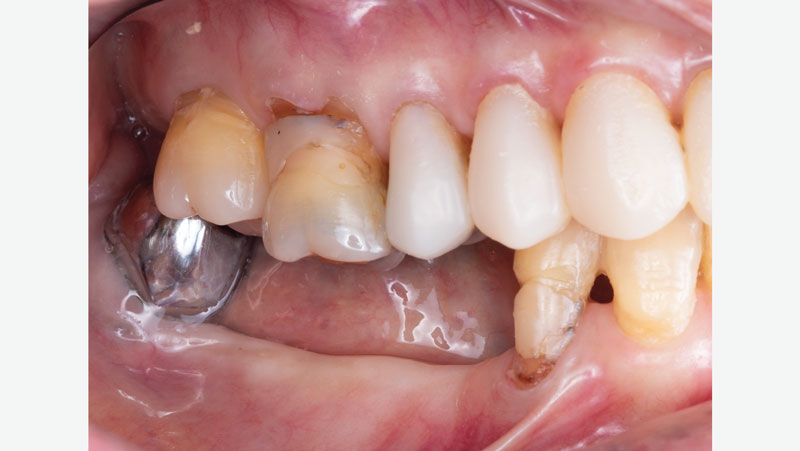

For any new crown to fit properly under an existing appliance, the crown must conform to its clasps, rests and axial contours. It’s important to pay close attention to the fit of the existing appliance.

For existing partials, examine the occluding tooth contact, the position of the tongue, how the retentive and reciprocal arms are placed, and how it rests on the occlusal surface of the crown. Be sure to also examine the patient’s oral environment when the partial is removed, noting the spacing and the gingival region around the crown.

Original crown without partial

Partial over original crown